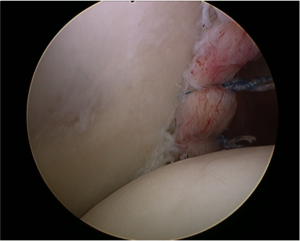

Consequently, a subchondral cleft (labrum and capsule attached but no tear) may be a normal finding.[3] Surgeons should be aware that while anterior capsule anatomy is quite variable, the posterior capsular insertion tends to be more homogenous in appearance among patients (Figure).

Associated intra-articular pathology such as superior labrum anterior posterior (SLAP) lesion, rotator cuff lesions or a paralabral cyst should be also assessed (Figure). Unlike spinoglenoid cysts, posterior or posterior-inferior labral cysts rarely results in impingement of the suprascapular nerve and suprascapular neuropathy.

Contrast enhancement during magnetic resonance arthrogram (MRA) is of great value and will increase the sensitivity of magnetic resonance imaging (MRI) in identifying a soft tissue injury (cartilage, rotator cuff, labral tears (Figure), a patulous capsule (Figure), reverse humeral avulsion of the glenohumeral ligaments (rHAGL, Figure), associated findings such as paralabral cysts) (Figure).

In patients with purely soft tissue injuries and no associated bone loss or fracture, then posterior capsulorraphy (ie, capsular shift) and labral repair are the treatments of choice. The use of arthroscopy in these cases has greatly surpassed that of open procedures primarily due to the less-invasive nature of the procedure, improved shoulder mechanics postoperatively, decreased scarring, and the ability to address concomitant lesions including posterior humeral avulsions of the glenohumeral ligament. It may reveal subtle lesions such a small crack or fissuring within the posterior labrum (hidden lesion or “Kim lesion”).